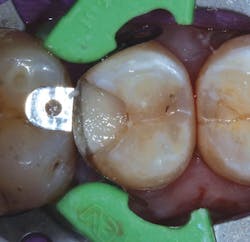

When a carious lesion and the Class II cavity preparation extend near to or apical to the cementoenamel junction, the sandwich technique can be used. The technique is described as a layering of various restorative materials within the cavity preparation. It involves placing RMGI at the base of the cavity preparation, followed by curing and the addition of composite restoratives to complete the restoration. If the remaining layers of composite resin completely encase the RMGI, it is considered a "closed" sandwich technique. If the RMGI is exposed to the oral environment at the base of the restoration, it is considered an "open" sandwich technique (figures 1a and 1b).

Figures 1a and 1b: RMGI sandwich techniques

This technique is not new and was originally proposed by Suzuki and Jordan. (4) According to Liebenberg, "The open-sandwich technique allows the least amount of microleakage of the various direct restorative options currently available." (5,6) This occurs because traditional composite bonding at the cavosurface and interproximal sites often have a complex combination of substrates that include enamel and varying levels of dentin, depending on the depth of the lesion. Liebenberg continues, "For dentin bonding, it appears far easier to achieve a seal than to maintain it, and in vivo studies have confirmed that resin-dentin bonds degrade in the oral cavity." (5,7)